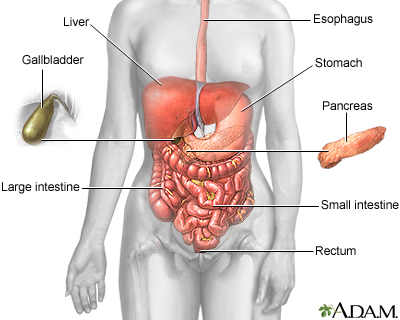

Intestinal obstruction and Ileus

Paralytic ileus; Intestinal volvulus; Bowel obstruction; Ileus; Pseudo-obstruction - intestinal; Colonic ileus; Small bowel obstruction

Intestinal obstruction is a partial or complete blockage of the bowel. The contents of the intestine cannot pass through it.

Causes

Obstruction of the bowel may be due to:

- A mechanical cause, which means something is partially of fully blocking the bowel

- Ileus, a condition in which the bowel does not work correctly, but there is no structural problem causing the obstruction